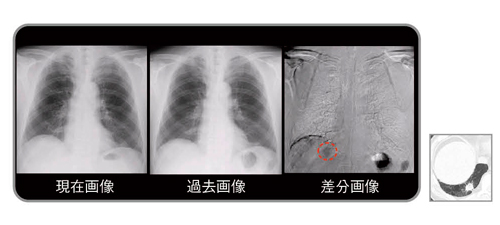

図1 差分画像の見え方

1980年代に商品化されたデジタル画像は,その後急速に普及し,2010年代の今ではほとんどの医療用画像はデジタル化され,モニタにより診断や治療が行われている1)。本稿で紹介する経時的差分法(temporal subtraction:TS)は,現在画像から過去画像を自動的に引き算して,変化のあった病変のみを強調して表示する手法で,新しく出現した病変を黒く表示し,消失した病変は白く表示させることで読影を支援するシステムである(図1)。

左上肺野の小結節出現(黒く表示),右中肺野の肺炎消失(白く表示)

従来の比較読影に,さらに差分画像を追加することにより,正常肺構造や既存肺病変に隠れがちな新規病変は,病変のみが明瞭に描出されるようになるため,読影時の気づきに大きな貢献が期待できる。また,従来の読影法のように一か所ごとに病変を見比べるのではなく,差分画像を一瞥するだけで胸部全体の変化のある病変だけを把握でき,読影時間の短縮につながることが期待できる。